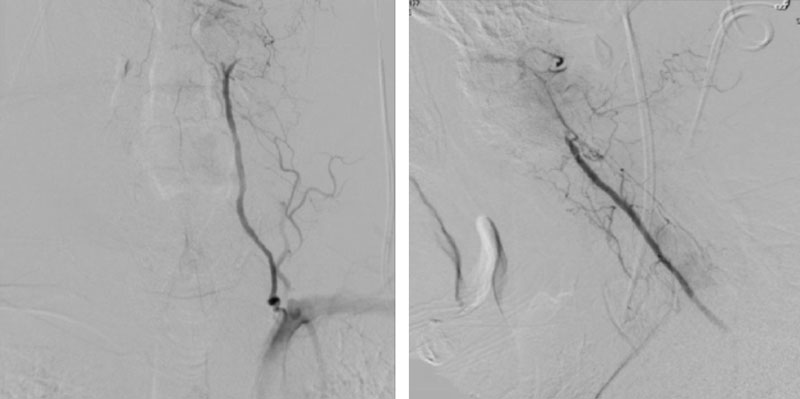

CTA of the neck and brain reveal that the left Vertebral Artery is completely occluded at approximately the C1-C2 level with extensive hypertrophic degenerative osseous changes from C1-C3. Retrograde flow into the post PICA left Vertebral Artery is observed from the co-dominant right Vertebral Artery which appears to be the primary supply into the basilar circulation. No significant Posterior Communicating arteries are observed on either the right or left Carotid Artery on the CTA imaging (Figure 1).

We performed conventional catheter angiography with provocative testing to reproduce his symptoms. The right Vertebral Artery is the codominant primary supply to the basilar circulation with reflux into the distal left Vertebral Artery that is occluded (Figure 3).

During neutral positioning, the vertebrobasilar circulation fills briskly from the Right Vertebral Artery. (Figure 4)